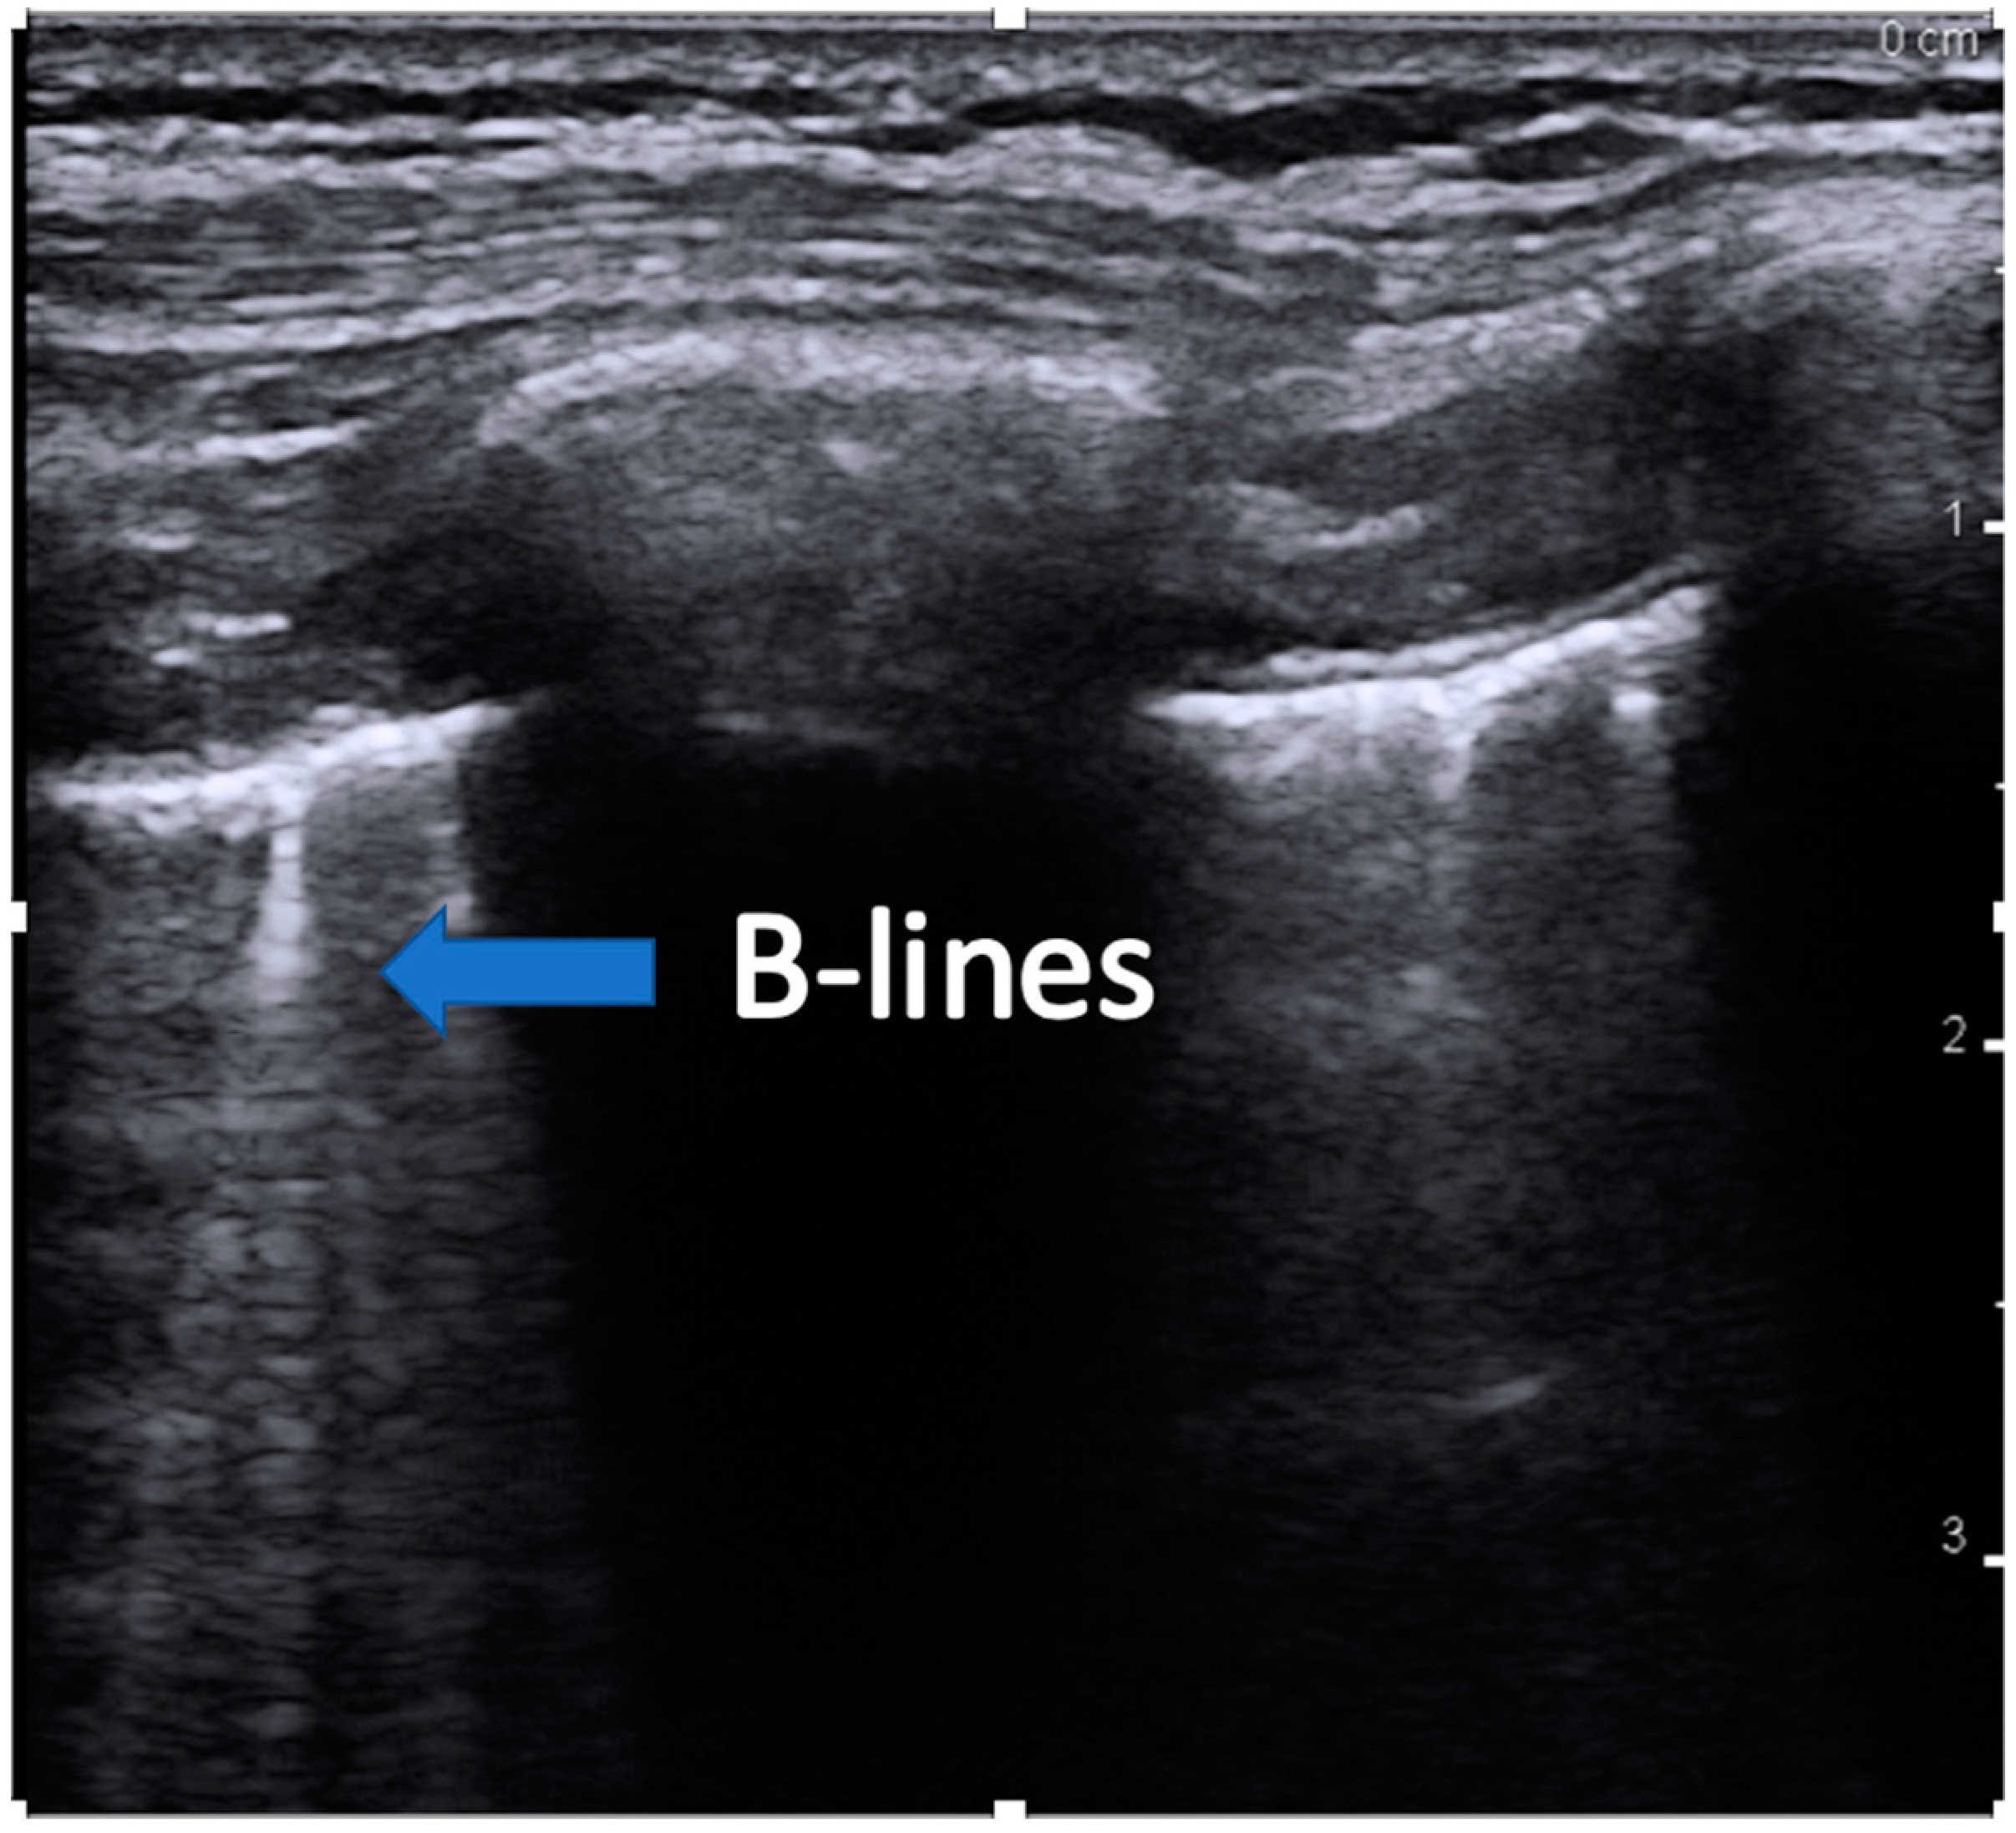

- B-lines are created when air is replaced in the alveoli by fluid, septal thickening, or other interstitial lung disease and which transmit the sound waves. B-lines originate at the pleural line and are long, vertical hyperechoic lines traversing the entire image depth (Figure 2). Up to two B-lines per rib space are normal, especially in dependent areas of the lung.

Figure 2. Image showing an example of B-lines. The blue arrow indicates the long hyperechoic lines that continue the full depth of the image, indicating replacement of air-filled alveoli.